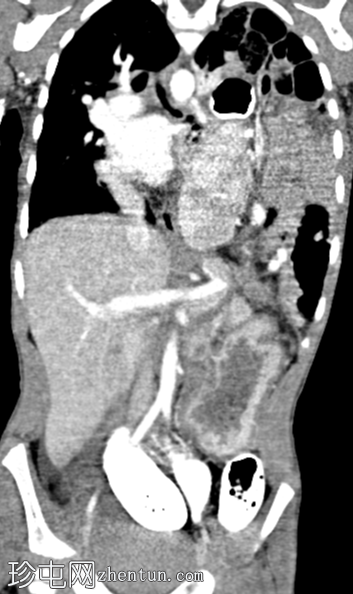

正面

消化道造影检查显示食管口径正常,胃明显延长,延伸至盆腔区域。

左胸腔可见囊性透亮区,与腹部相连,导致心脏轮廓向右侧移位。